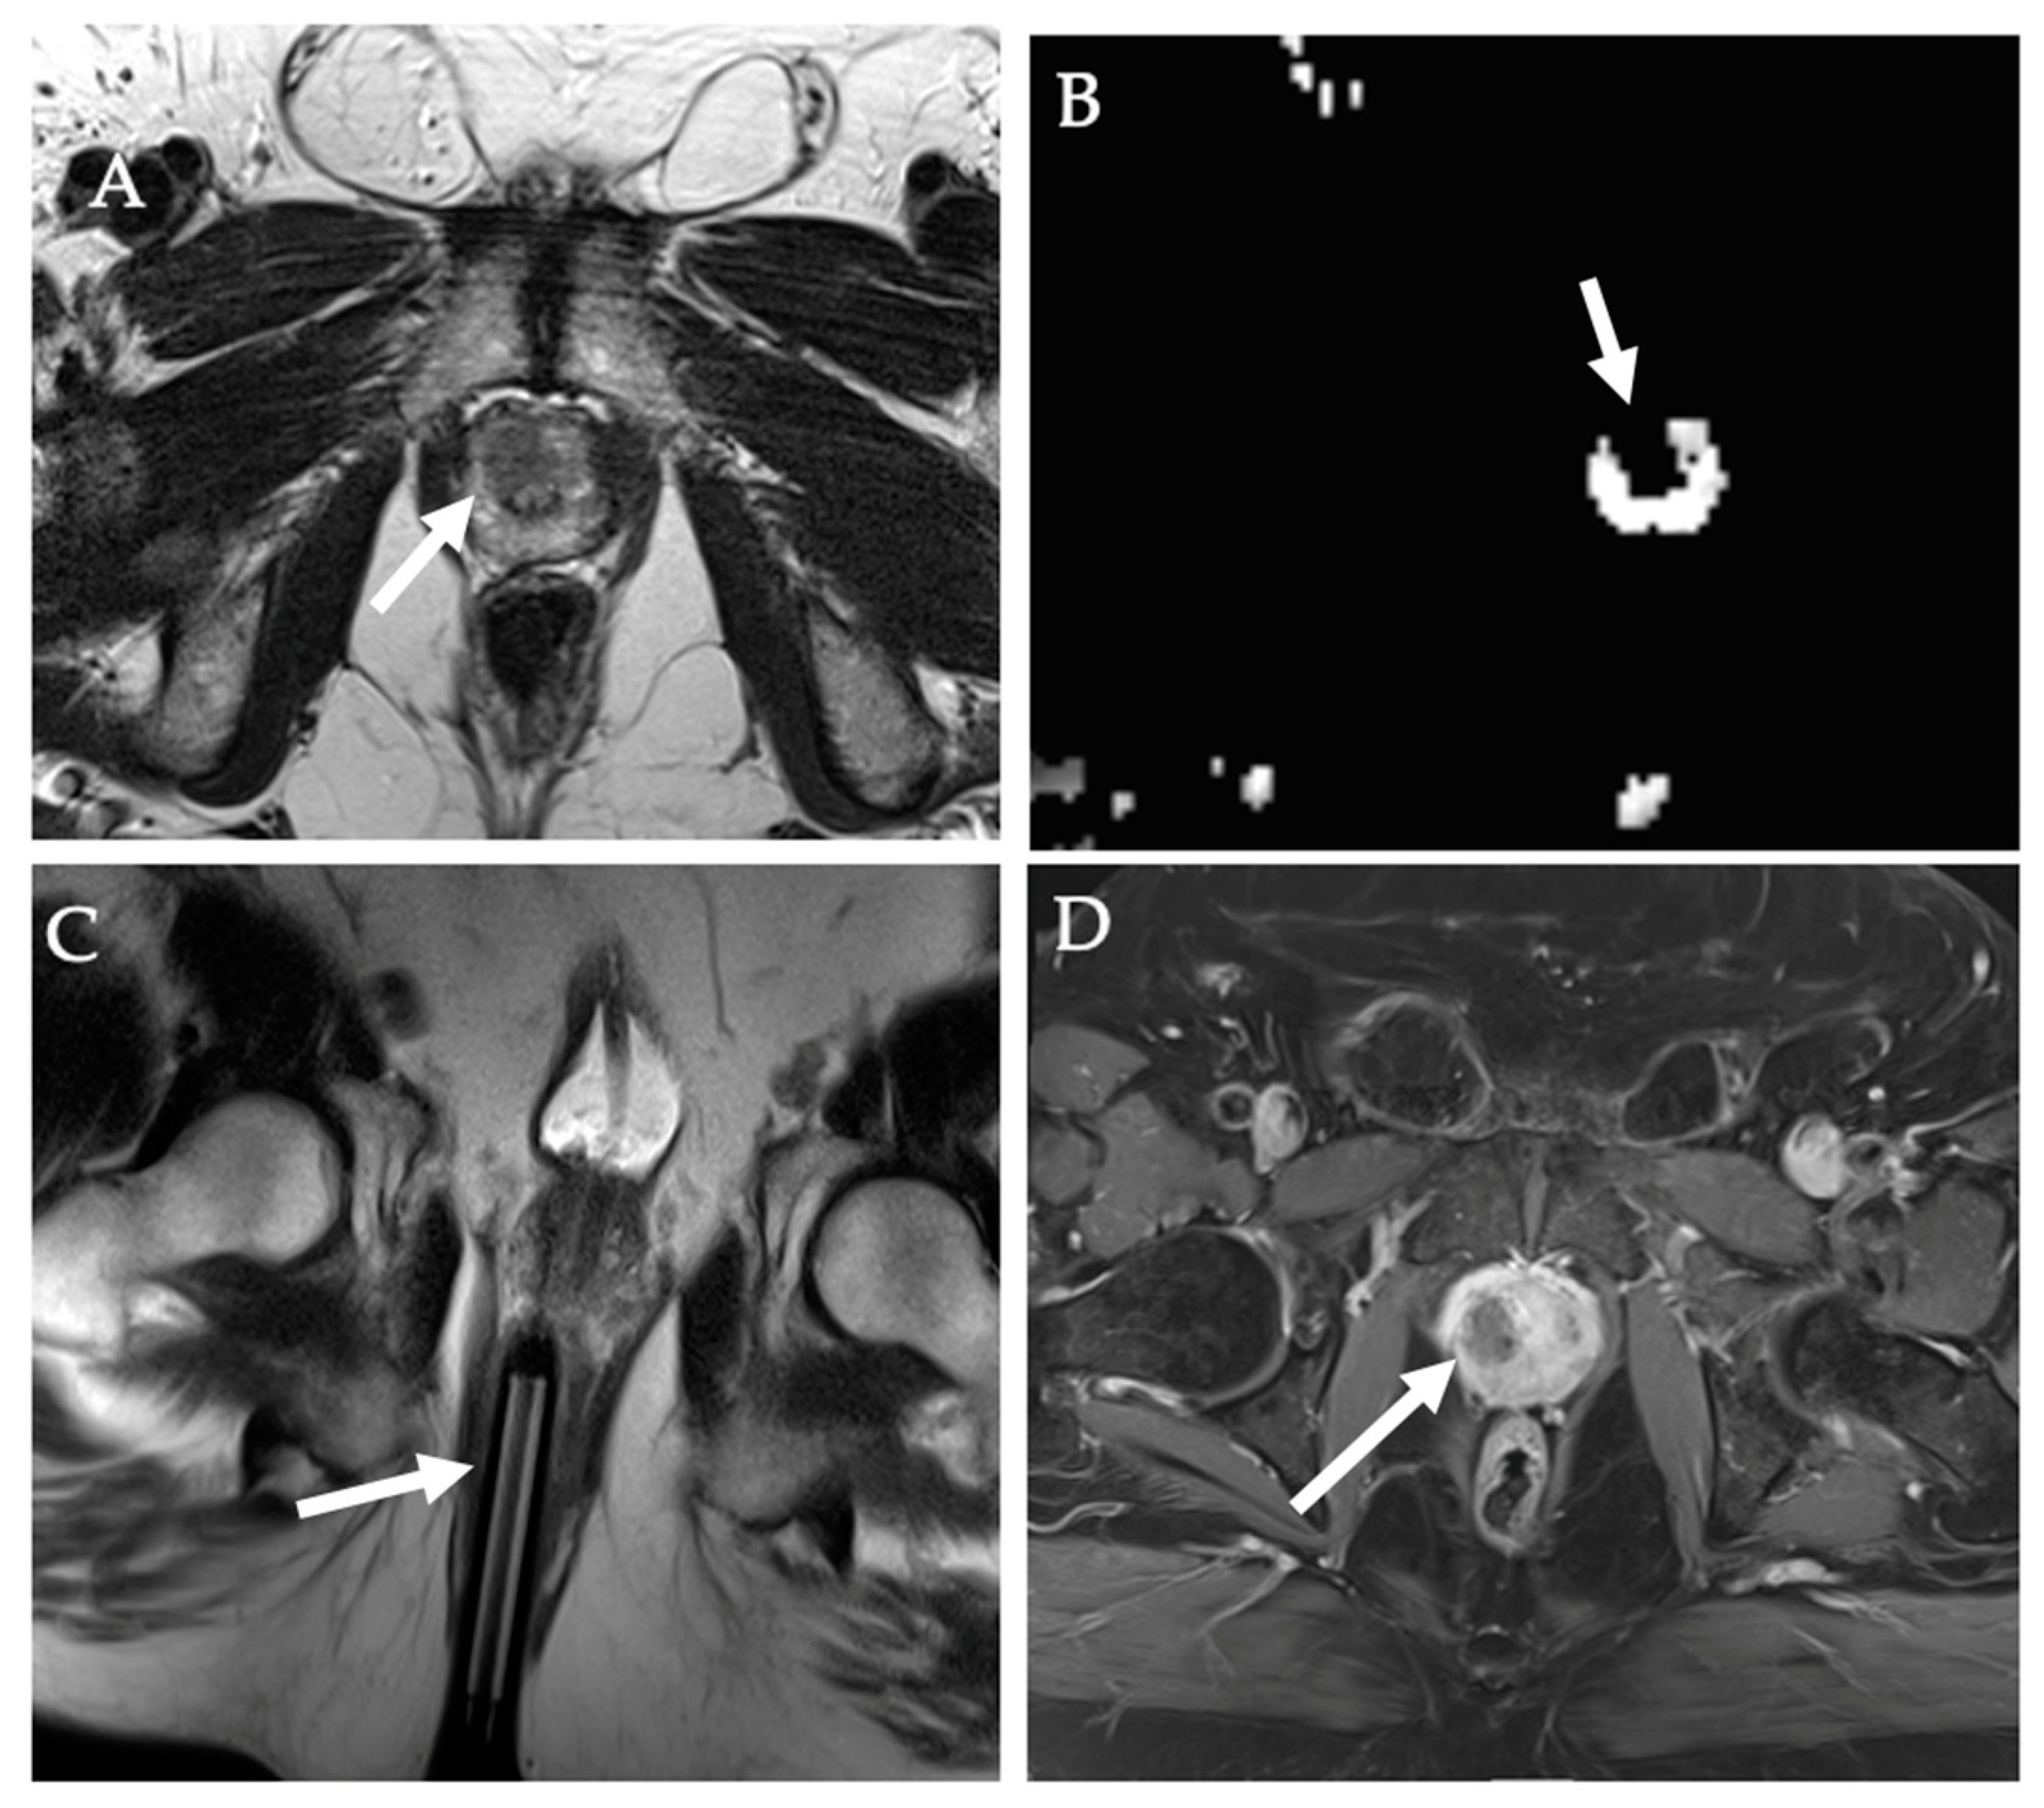

9. Prostate Tumors